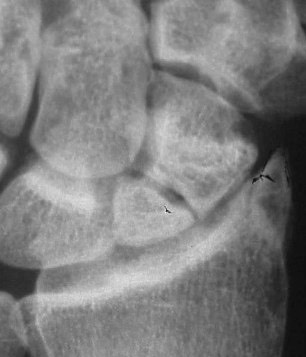

This X-ray shows a scaphoid nonunion.  The scaphoid fracture had never healed properly and now is not able to heal on its own.  This can often quite a bit of dysfunction in the wrist and will need to be treated.